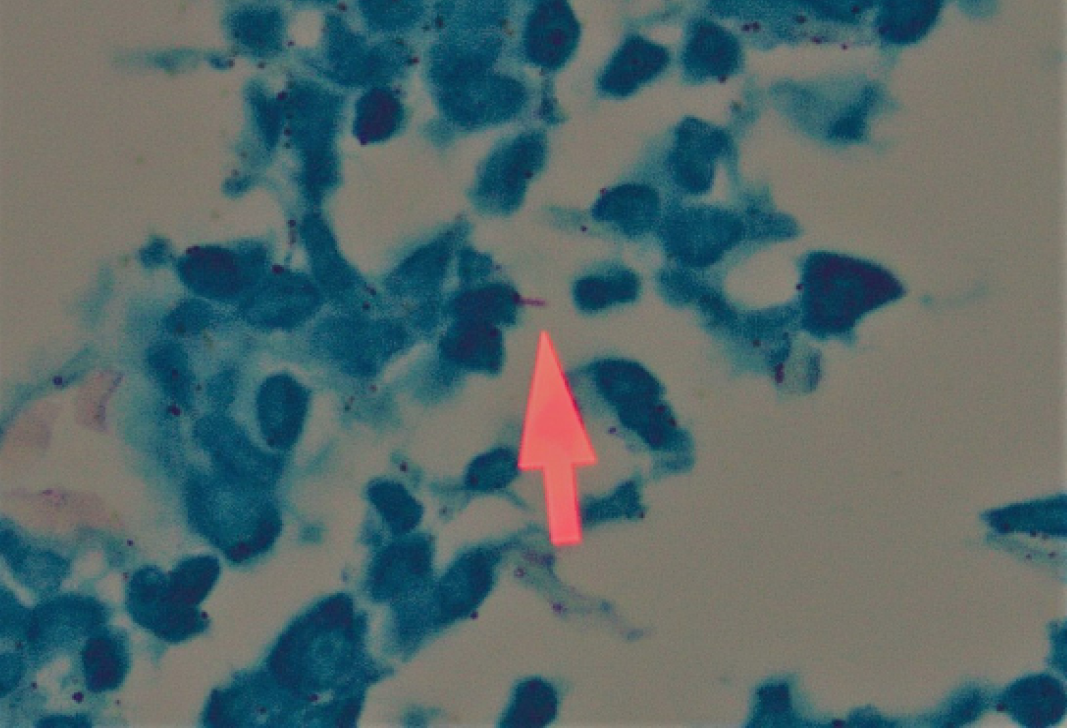

On altı yaşındaki kadın hasta sık tonsillit geçirme ve kronik bir boğaz ağrısı şikayetiyle kliniğimize başvurdu. Hastanın fizik muayenesinde tonsiller bilateral simetrik grade 4 hipertrofik, yapılan endoskopik nazofarinks ve larienks muayenesi ise doğal izlendi. Tonsil yüzeyinde herhangi bir ülsere alan ya da patolojik bir görünüm mevcut değildi. Hastanın son iki yıldır yılda 8-9 kez geçirdiği tonsillit atakları ve çok sık yaşadığı boğaz ağrısı dışında ek bir şikayeti, ek bir hastalığı ya da ilaç kullanım öyküsü yoktu. Fakat hastamız ailesiyle değil bir öğrenci yurdunda kalmaktaydı. Preoperatif dönemde yapılan rutin biyokimya ve hemogram tetkiklerinde herhangi bir anomali izlenmedi. Çekilen posteroanterior (PA) akciğer grafisi normal olarak yorumlandı. Sedimantasyon 10 mm/1.saat, CRP 3.11 mg/lt, beyaz küre (WBC) sayısı 6.6 hücre/mm3, hemoglobin (Hgb) 12.5 gr/dl idi. Hastaya genel anestezi altında tonsillektomi operasyonu yapıldı. Tonsil dokuları kolaylıkla diseke edilerek çıkartıldı. Kliniğimizde rutin bir uygulama olarak çıkarılan tonsil dokuları patolojik incelemeye gönderildi. İki hafta sonra patoloji sonucu kazeifiye granülamatöz tonsillit olarak raporlandı. Bunun üzerine hasta İnfeksiyon Hastalıkları ve Klinik Mikrobiyoloji Anabilim Dalı tarafından değerlendirildi. Serolojik testlerde anti-Toxoplasma IgM ve G negatif, anti-CMV IgM negatif, anti-CMV IgG pozitif, anti-HIV negatif, syphilis ELISA negatif, Brucella aglütinasyon testi negatif olarak sonuçlandı. Uygun materyal olmaması nedeniyle tonsil dokusunda tüberküloz kültürü ve balgamda “aside dirençli bakteri (ARB)” boyama ve kültürü yapılamadı. Tüberkülin deri testi 20 mm ve tonsil dokularından yapılan Ziehl-Neelsen boyamasında iki alanda pozitif boyanan birer tüberküloz basili saptandı (Resim 1 ve 2). Akciğer, larinks ve diğer organ incelemelerinde tüberküloz tespit edilmedi.